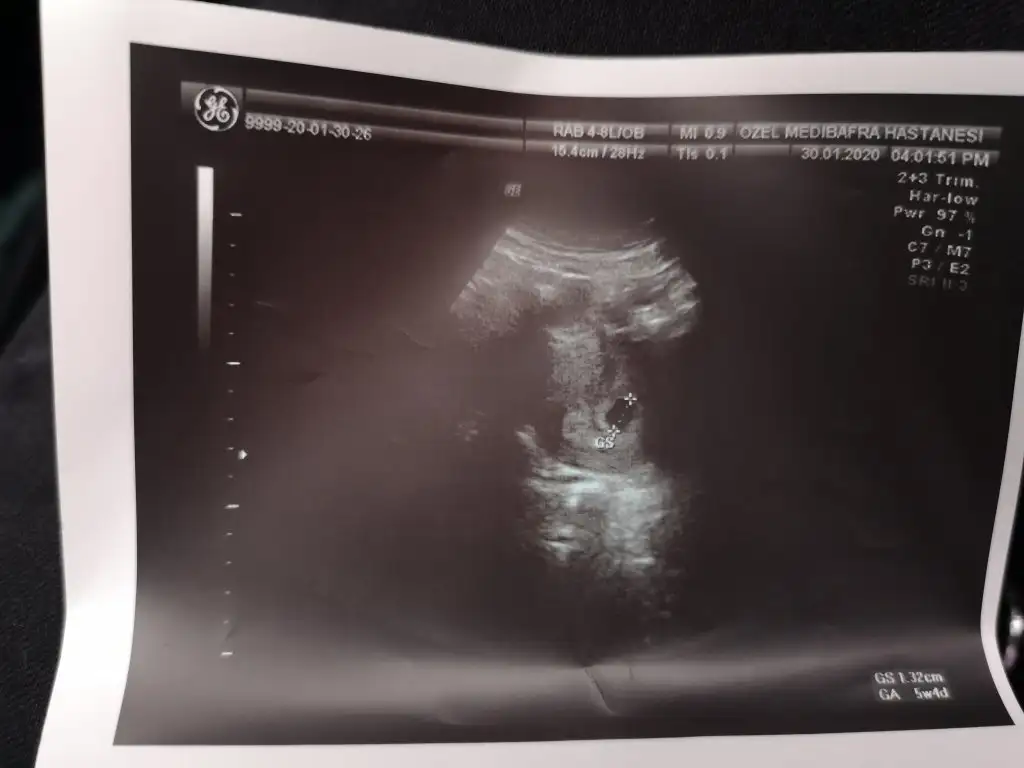

Bugün 6+1 im ama 5+4 çıktı. Geç döllenme dedi. 10 gün sonra tekrar çağırdı. Kan sulandırıcı da vermedi. Bu doktora devam etmeyeceğim zaten. Diğer dr izinde olduğu için randevu almıştım.bmbm ne yaptin canim doktordan geldinmi

HimmmBugün 6+1 im ama 5+4 çıktı. Geç döllenme dedi. 10 gün sonra tekrar çağırdı. Kan sulandırıcı da vermedi. Bu doktora devam etmeyeceğim zaten. Diğer dr izinde olduğu için randevu almıştım.